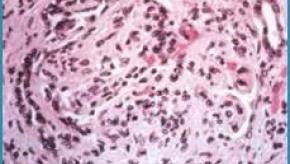

Read ArticleEarlier ACL reconstruction and a lower risk of knee osteoarthritis

A preclinical study by HSS investigators found that earlier anterior cruciate ligament (ACL) reconstruction led to lower immune cell activity, less inflammation and fewer joint changes associated with knee osteoarthritis compared to delayed surgery.